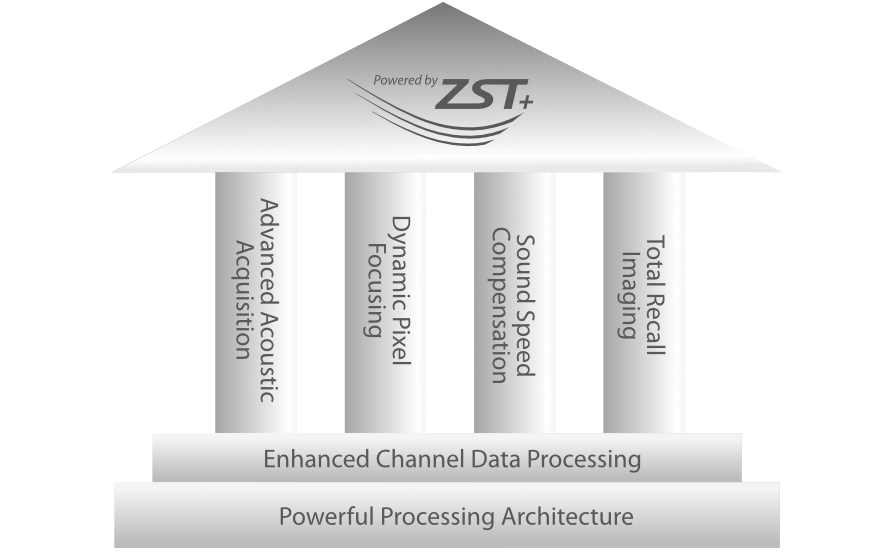

ZST + Taraf?ndan Desteklenen Eksiksiz ??z├╝m

ZST+ platformu, ultrason evrimini temsil eden ola?an├╝st├╝ bir yeniliktir. Ultrason ?l?├╝mlerini geleneksel ???n bi?imlendirmeden kanal verilerine dayal? i?lemeye d?n├╝?t├╝r├╝r. Mekansal ??z├╝n├╝rl├╝k, zamansal ??z├╝n├╝rl├╝k ve doku homojenli?i aras?ndaki geleneksel dengeli s?n?rlaman?n ├╝stesinden gelir ve kesintisiz iyile?tirmelerle s?n?rs?z g?r├╝nt├╝leme ??z├╝mleri i?in ola?an├╝st├╝ g?r├╝nt├╝ kalitesi sunar.